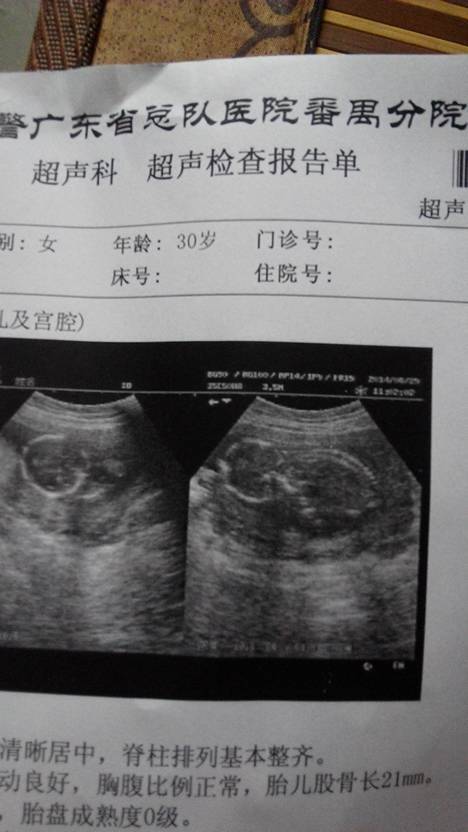

大家帮我猜猜是男宝还是女宝,怀17周,双顶径37mm股骨长21mm,胎心率14O次/分,胎盘位于后

你好,从BC单上面的数据来判别胎儿性别的行为是不科学的,顿则通最梅印过耻破BC判别是指医生通过BC显示屏看,而不是看BC单